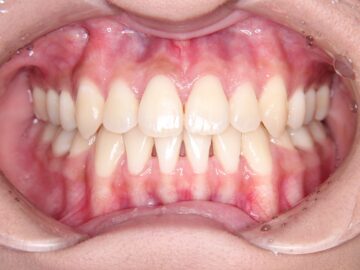

治療後

歯ぐきが薄く口唇がわずかに突出しているため、小臼歯抜歯での治療を勧めた。

| 抜歯部位 | 上顎左右測第一小臼歯、下顎左右測第一小臼歯 |